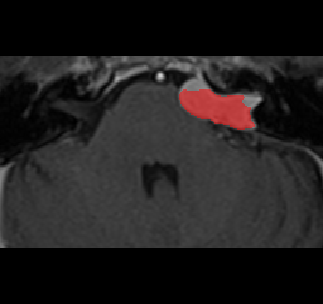

Recently, deep learning methods have achieved state-of-the-art performance in many medical image segmentation tasks. Many of these are based on convolutional neural networks (CNNs). For such methods, the encoder is the key part for global and local information extraction from input images; the extracted features are then passed to the decoder for predicting the segmentations. In contrast, several recent works show a superior performance with the use of transformers, which can better model long-range spatial dependencies and capture low-level details. However, transformer as sole encoder underperforms for some tasks where it cannot efficiently replace the convolution based encoder. In this paper, we propose a model with double encoders for 3D biomedical image segmentation. Our model is a U-shaped CNN augmented with an independent transformer encoder. We fuse the information from the convolutional encoder and the transformer, and pass it to the decoder to obtain the results. We evaluate our methods on three public datasets from three different challenges: BTCV, MoDA and Decathlon. Compared to the state-of-the-art models with and without transformers on each task, our proposed method obtains higher Dice scores across the board.